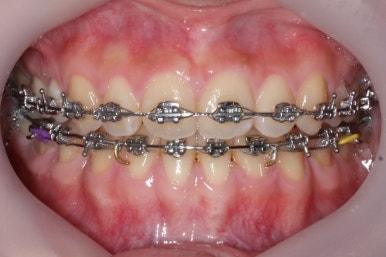

부산교정전문의 키다리아저씨치과에 처음 내원하셨을 때 당시의 입안 모습입니다.

윗니 뿐만 아니라 아랫니 부위에도 덧니가 관찰됩니다. 다른 앞니, 어금니 부위도 약간 삐뚤한 부분이 보입니다.